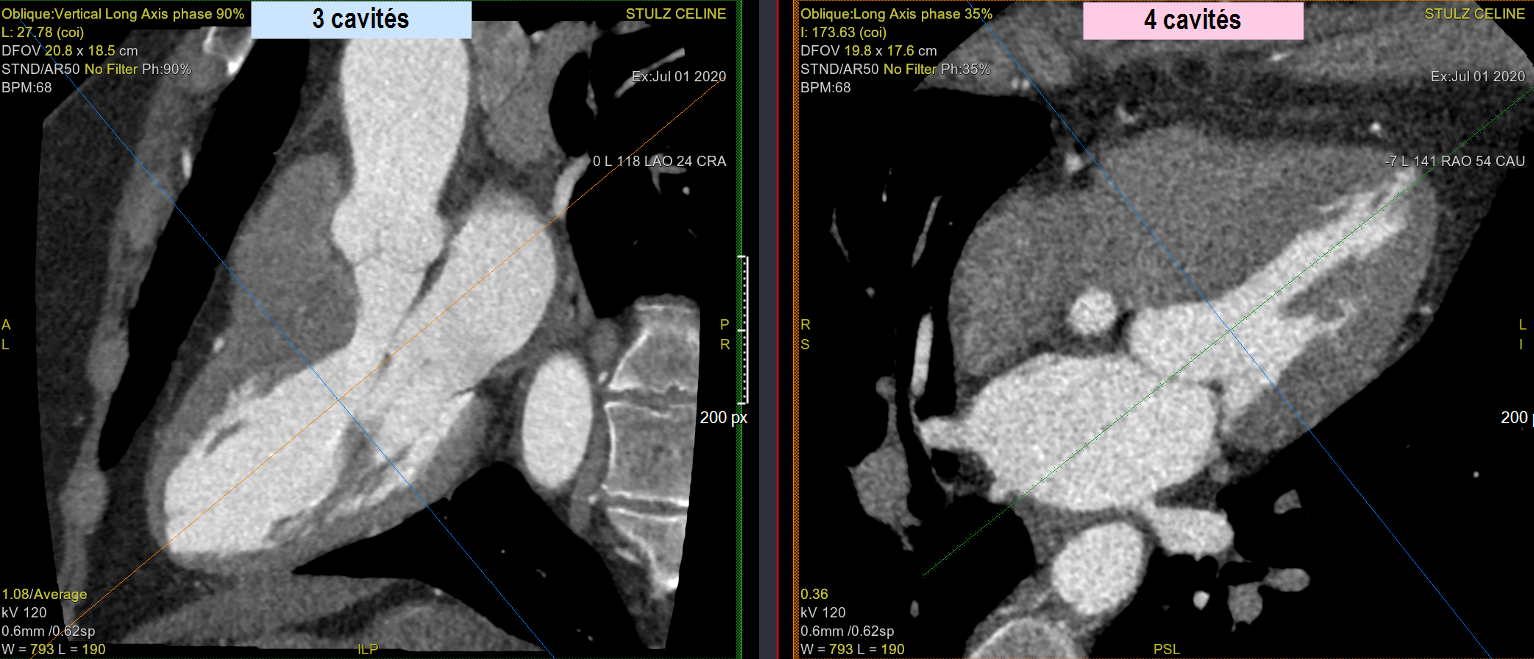

- Faire une analyse de perfusion du myocarde (on peut aussi le voir simplement sur Carestream)

3 cavités: 1 Ciné

4 cavités: 1Ciné puis 3 cinés sur les 3 segments en coronalé (a hauteur de la valve (basal), puis le milieur= les piliers (medio-cavitaire), puis territoire apical (apical)